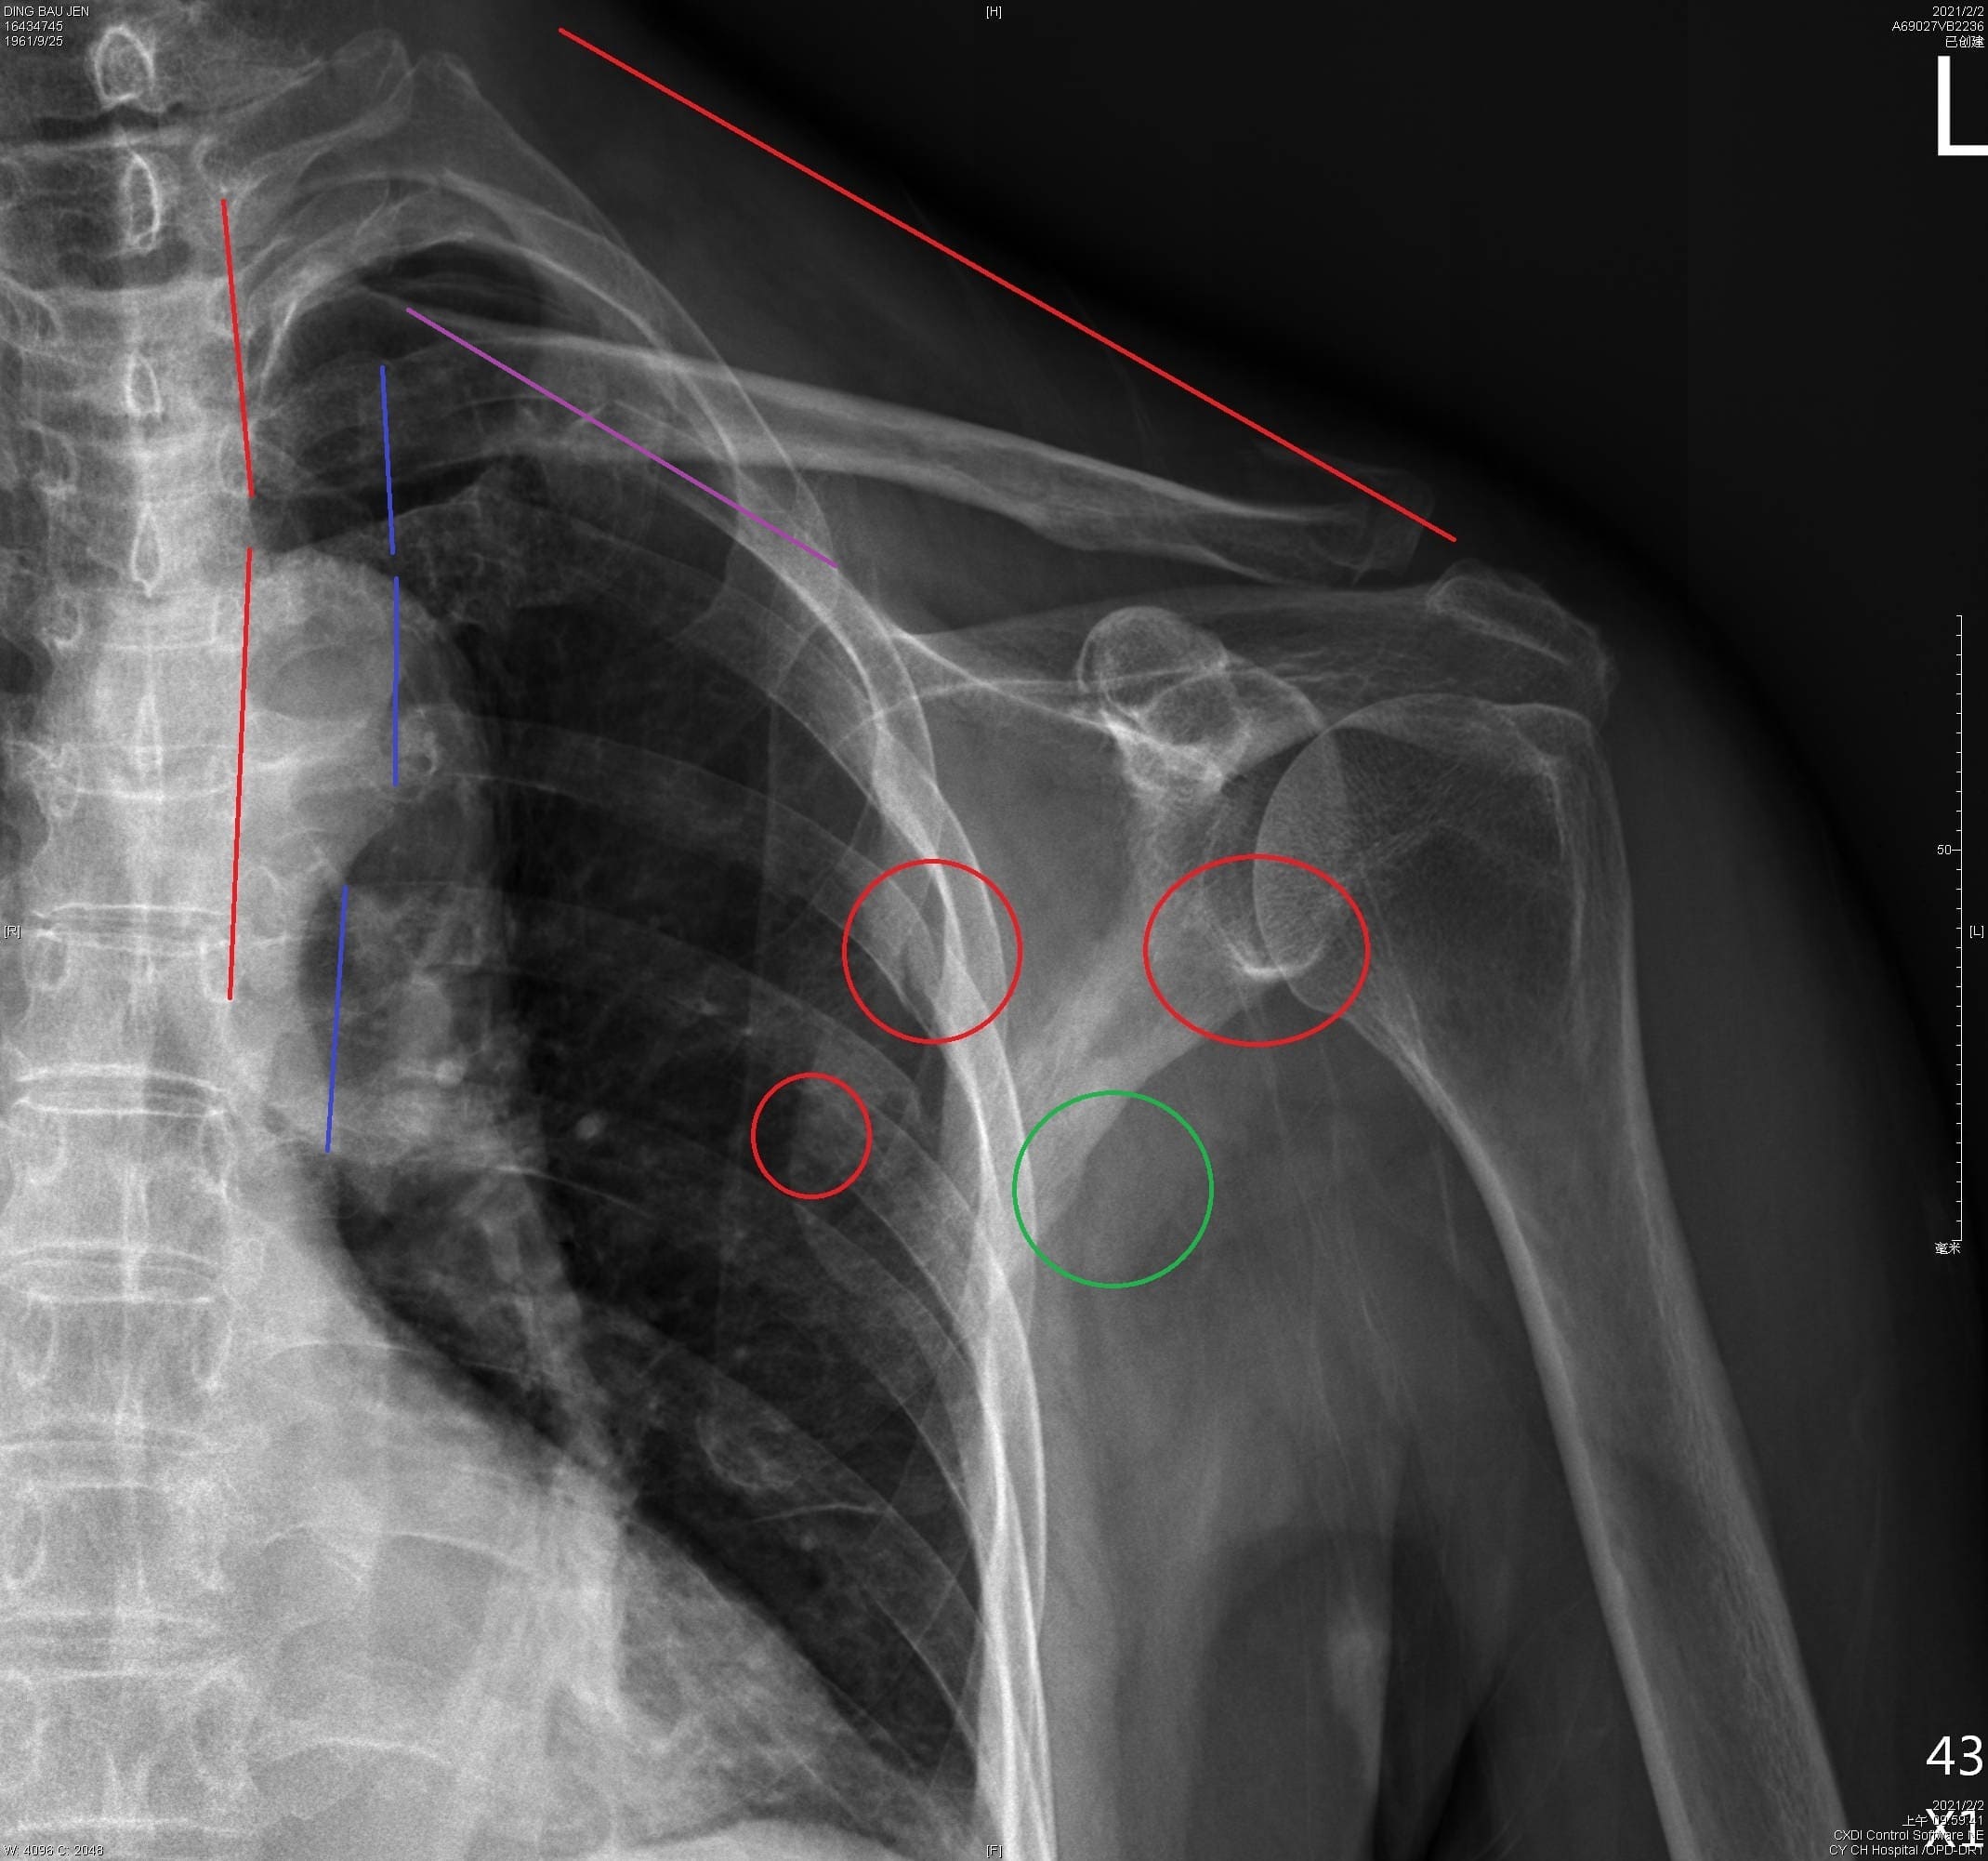

車禍肋骨與四肢骨折 無創傷手術